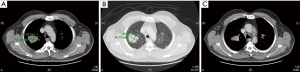

Enhanced chest and abdomen CT scan confirmed a right upper lobar pulmonary mass lesion with small necrotic changes with irregular edges (Figure 2A,B,C). Tru-Cut biopsy confirmed the diagnosis of non-small cell carcinoma, consistent with squamous cell carcinoma, moderately differentiated with prominent necrosis. However, complete staging performed which showed few but less than 1 cm in diameter of mediastinal lymph nodes in the right para-tracheal area, but no distant metastatic lesions found in the abdomen, brain or bones.